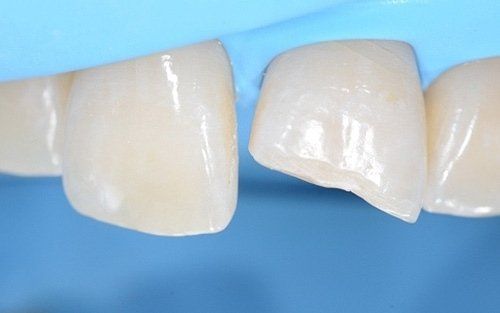

I denti da latte traumatizzati più spesso vanno incontro a necrosi con conseguente cambiamento di colore, divenendo grigiastri, segno della morte delle cellule della polpa dentaria. In altre occasioni, il dente può fratturarsi in maniera più o meno ampia: se il frammento viene ritrovato, potrà essere re-incollato in maniera invisibile, oppure verrà ricostruito con i materiali compositi.